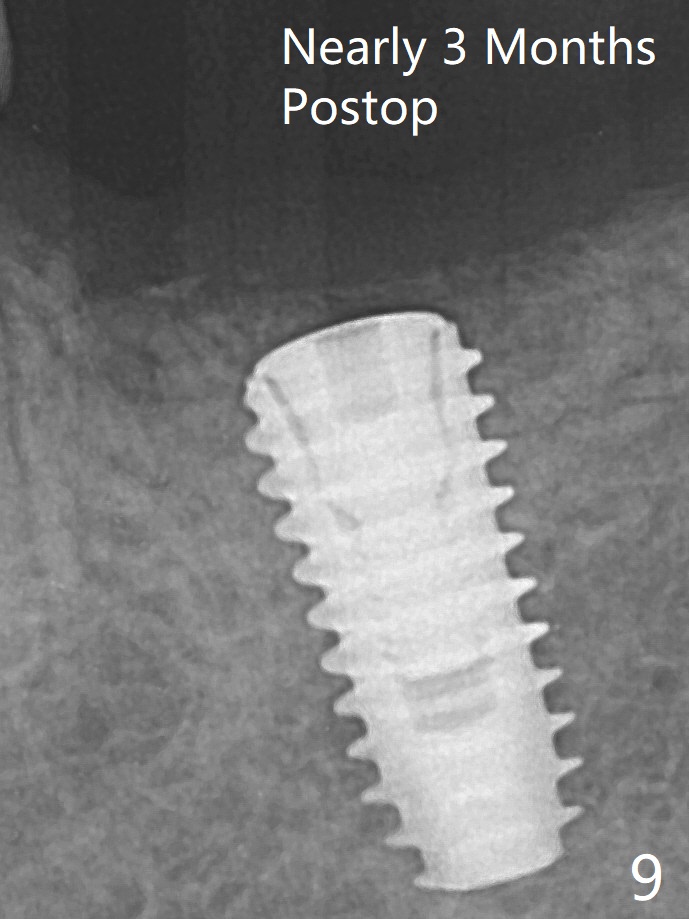

Allograft is placed around the fractured ridge (Fig.6*) before suturing. The ridge appears to have healed nearly 3 months postop (Fig.9). In uncover, the implant plateau is covered with bone; surgical handpiece is used to remove the overlying bone before removing the healing screw. Bone loss in the near future is expected to be minimal if more implants can be placed on the right side. A 5.5x4(4) mm abutment is placed 3.5 months postop (Fig.10).